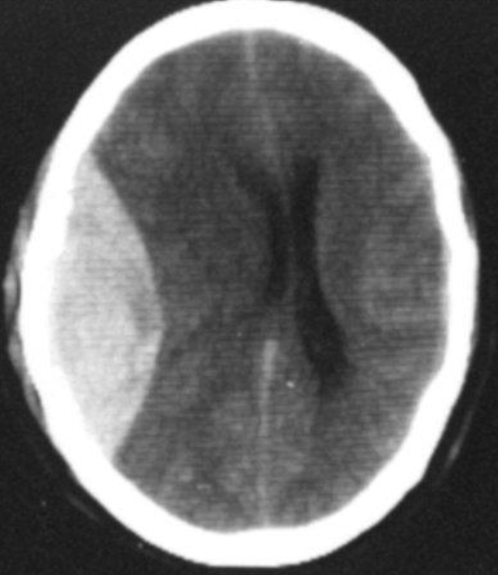

Epidural hematoma

- Convex inner margin (lens-shaped)

- High density area